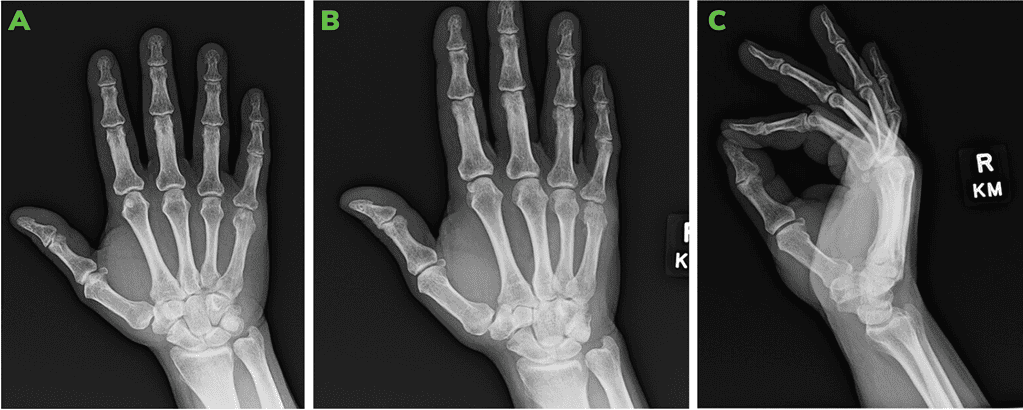

4-Weeks Post-Operative X-Rays: Ap [A], Oblique [B] And Lateral [C] Views.

Figure 3: 4-weeks post-operative X-rays: AP [A], Oblique [B] and Lateral [C] views.

The OSSIOfiber® Threaded Trimmable Fixation Nail allows patients to return to full activities much sooner compared to common metal screws. While restricted activity for 6-8 weeks post ORIF is usually needed, when using the OSSIOfiber® nail, by 4 weeks full weight bearing with no restriction to load is already allowed due to the strong rotational support of the implant, with no splint or cast needed.